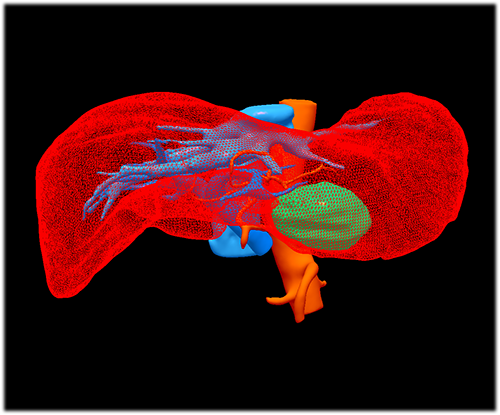

左肝外侧叶肝癌---左肝外侧叶切除